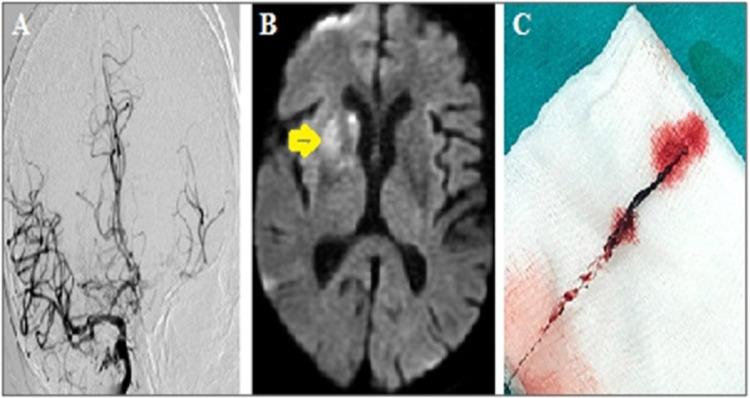

COVID-19 disease causes various neurological disorders. Of these, stroke is the most devastating and difficult to manage in epidemic conditions. An increase in the rate of acute ischemic stroke in hospitalized coronavirus patients and stroke with large vessel occlusion due to COVID-19 disease have been reported in recent publications. The management of these patients is difficult and becomes even more challenging in epidemic conditions. A 71-year-old man suddenly developed left-sided weakness while he was hospitalized for COVID-19 disease. Cerebral computed tomographic angiography showed a terminus of the right internal carotid artery. The occluded vessel was completely recanalized by endovascular therapy. Left-sided hemiparesis resolved completely. As a result of this study, cryptogenic stroke was considered in the etiology of stroke. In this report, we present a case of stroke with COVID-19, who developed large vessel occlusion accompanied by splenic infarction while hospitalized due to COVID-19 disease and was successfully treated with endovascular thrombectomy under epidemic conditions.

新型冠状病毒肺炎(COVID-19)可引发多种神经系统疾病。其中,中风最为严重,在疫情期间也最难处理。近期发表的文献报道了住院的冠状病毒患者急性缺血性中风发生率增加以及因COVID-19疾病导致的大血管闭塞性中风。这些患者的治疗难度很大,在疫情期间更是极具挑战性。一名71岁男性在因COVID-19疾病住院期间突然出现左侧肢体无力。脑部计算机断层血管造影显示右侧颈内动脉末端闭塞。通过血管内治疗,闭塞血管完全再通。左侧偏瘫完全缓解。基于本研究结果,中风病因考虑为隐源性中风。在本报告中,我们介绍了一例因COVID-19疾病住院期间发生大血管闭塞并伴有脾梗死的COVID-19相关性中风病例,该病例在疫情条件下成功接受了血管内血栓切除术治疗。